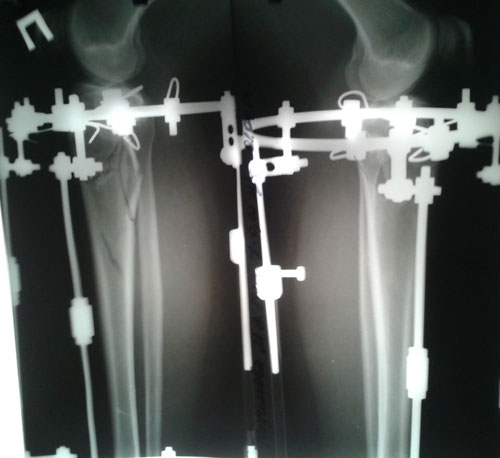

Дата операции 14.03.2017г.

Ротация (двухсторонняя)

Ножки на фиксации

Дата снятия аппаратов 28.06.2017г.

Срок лечения 103 дня.